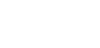

Per una visualizzazione immediata delle caratteristiche morfologiche dell’erosione dentale, ecco due esempi clinici che illustrano le differenti fasi del processo erosivo e le relative implicazioni diagnostiche.

Caso A

Erosione BEWE (Basic Erosive Wear Examination), rischio alto >14.

Paziente con bulimia nervosa per 12 anni, episodi fino a 10 al giorno, ad oggi risolta.